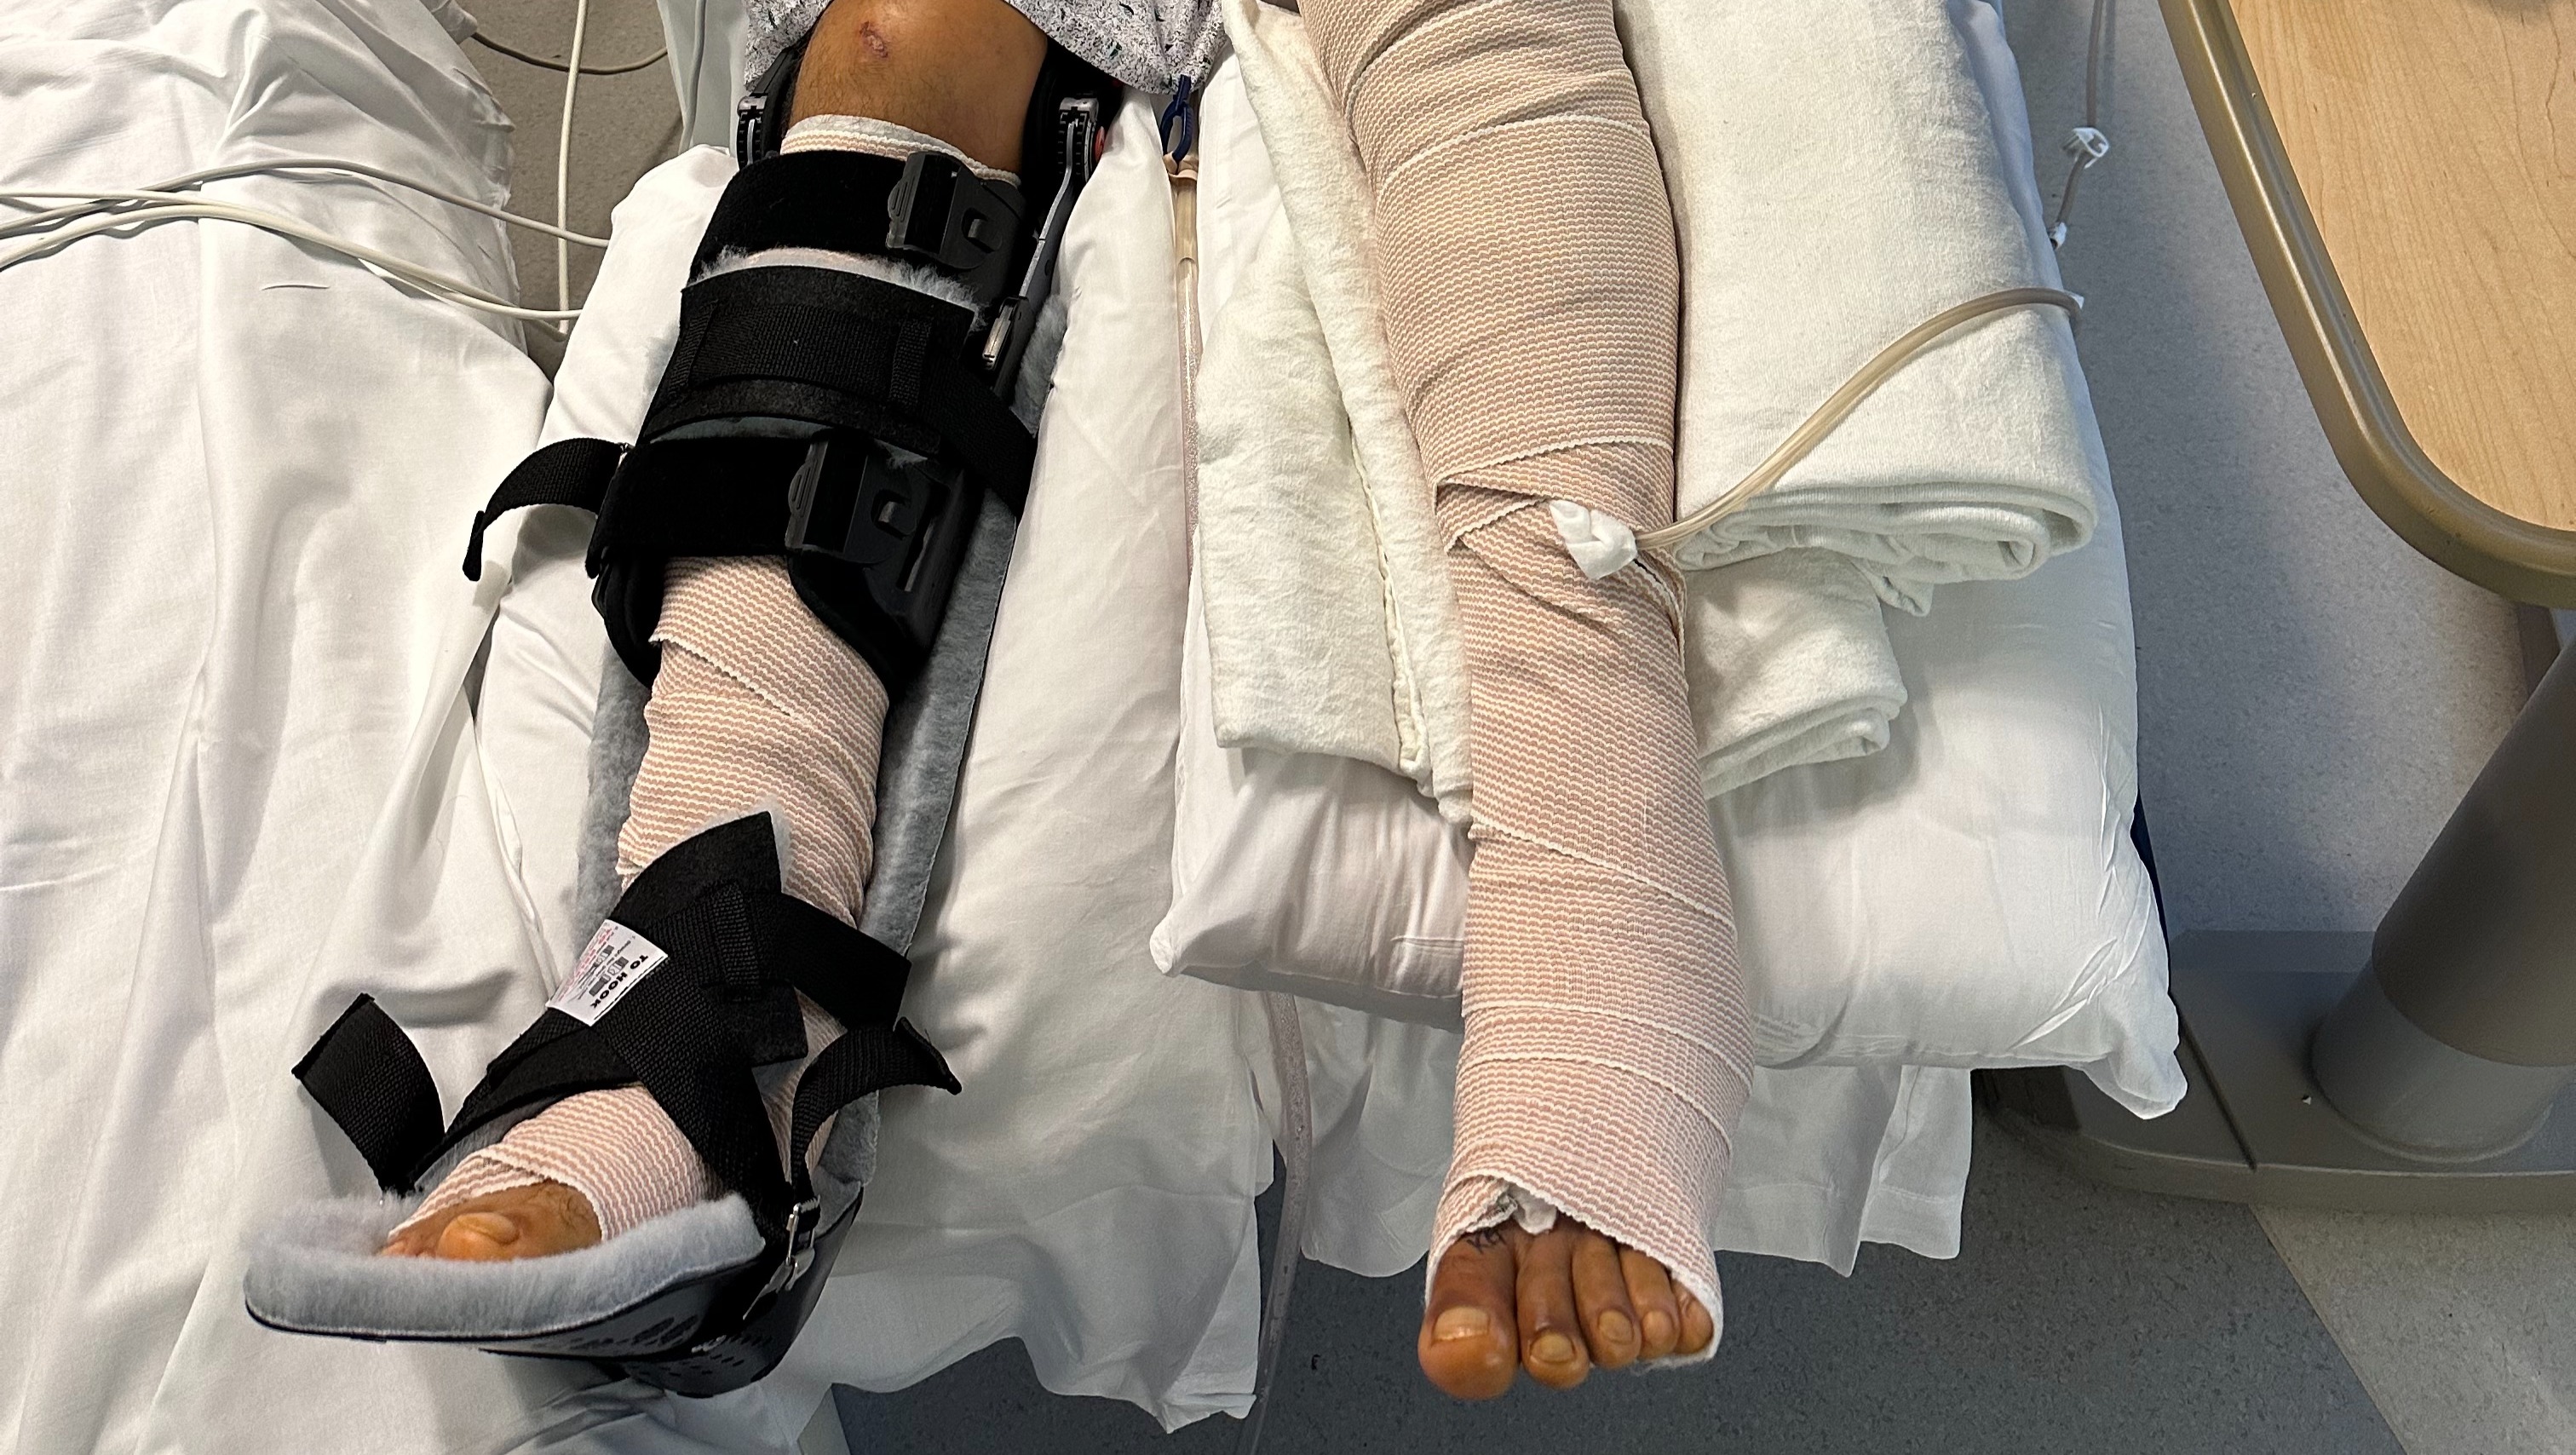

On August 23rd, Luis was severely injured in a hit-and-run. He was struck by a car on 676 that did not stop after they hit him. The accident inflicted serious injuries and wounds to his lower legs. He broke his tibia and ankle, injured his knee, endured major wounds and more. We're thankful for the passersby who stopped on the highway, the state troopers who wrapped his legs, the EMTs and the incredible staff at Jefferson Hospital in Philly for saving his life, and his legs.

It's going to be a long road to recovery; Luis won't be walking on his own for 4-6 months and even with insurance, he's going to have many medical, physical therapy and medical equipment bills that won't be fully covered, as well as lots of other things he'll need to stay comfortable and in good spirits.